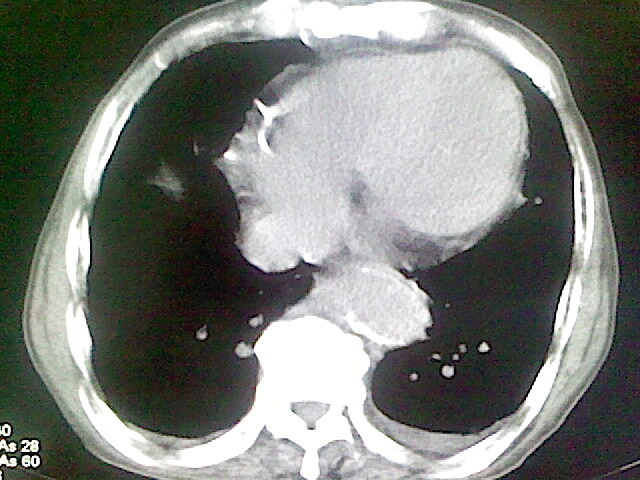

以下是引用zsl6918在2008-8-28 16:49:00的发言:[br]双肺炎性病灶,食管狭窄估计与心房增大压迫所致。

以下是引用xulianj在2008-8-28 20:36:00的发言:[br]慢支肺气肿伴感染,右上肺陈旧性结核;食道建议胃镜检查。

以下是引用wqs571018在2008-8-28 21:18:00的发言:[br]慢支继发感染,右上肺陈旧性结核;食道建议胃镜检查。